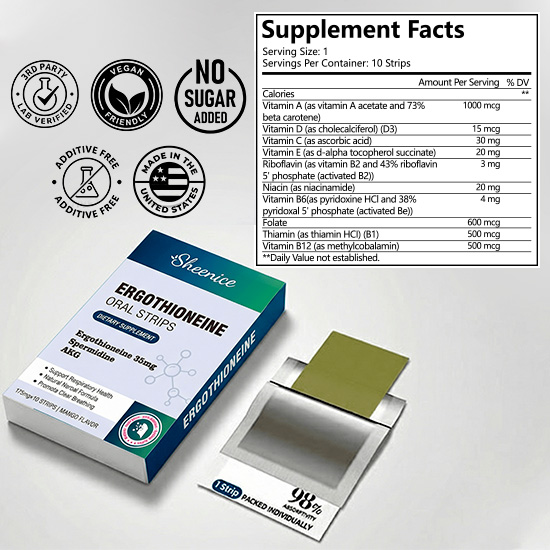

4 Synergistic Ingredients:

Sheenice is carefully formulated, not random. Each strip contains a precise blend of Organic Milk Thistle Seed, Organic Schisandra, Organic Cornus, and Taurine. These four work together to help clear lung toxins, reduce inflammation, support alveolar elasticity, and promote deeper, smoother breathing.

Organic Milk

Thistle Seeds:

Rich in antioxidants, helping to reduce oxidative stress and

support the lungs' natural defense against environmental pollutants.

Organic

Schisandra:

Traditionally used to

strengthen and soothe the lungs, promoting smoother breathing and relieving lung

fatigue.

Organic

Dogwood:

By

nourishing the liver and kidneys, it helps balance the body's energy flow,

indirectly supporting lung function and respiratory health.

Taurine:

Helps regulate

inflammation, supports airway health, and maintains normal lung function.